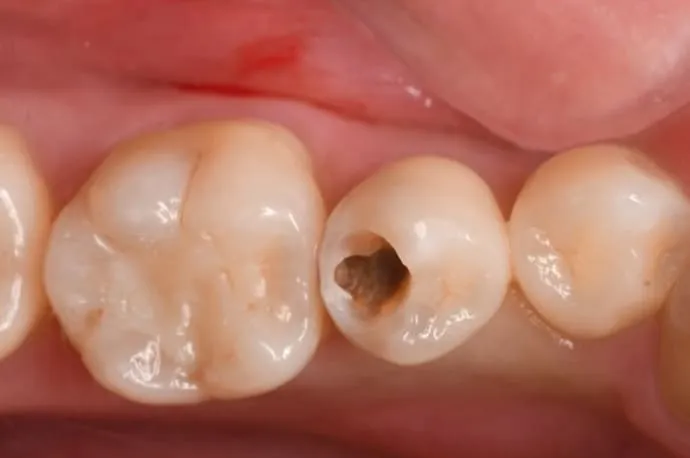

虫歯除去の流れ

一見すると穴が空いていないように見えますが、内部で虫歯が広がっている状態です。

歯の表層を削ると、中は大きな空洞になっています。

虫歯を染める専用の薬剤を使い、どこまで虫歯が広がっているかを確認します。

染色液で染まった部分を丁寧に除去し、再度染めて確認します。この作業を繰り返し、染まらなくなるまで行います。虫歯は健康な歯に比べて柔らかいため、回転切削器具だけでなく、手作業で少しずつ取り除くこともあります。染色液だけでなく、触ったときの硬さも目安にします。

虫歯の除去が完了すると、かなり大きな空洞になっています。中央の少し青く染まっている部分は、歯の神経が露出している状態です。このように大きな虫歯の場合は、修復の前に根管治療が必要になります。